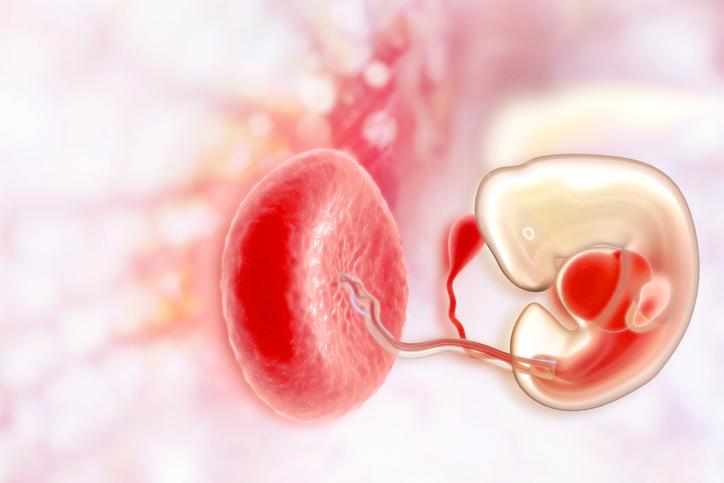

Desarrollo del embrión en el segundo mes de embarazo

Durante el segundo mes de embarazo el desarrollo del embrión es impresionante. A continuación destacamos los hitos más importantes del desarrollo embrionario durante el segundo mes de embarazo.

- La placenta forma pequeñas vellosidades que contienen vasos sanguíneos que comunican el cordón umbilical con la placenta. A través de estos vasos sanguíneos llega la sangre de la madre al feto. A partir de la octava semana, es decir, al final del segundo mes, el embrión empieza a alimentarse mediante el cordón umbilical.

- El embrión está flotando en el líquido amniótico, que le protege y proporciona el ambiente ideal para desarrollarse.

- El embrión empieza a presentar rasgos faciales como la forma de los párpados, la nariz, las orejas y el labio superior.

El embrión empieza el mes 2 de embarazo midiendo entre 2 y 3 mílimetros y al final del segundo mes de embarazo ya mide 1,6 centímetros y pesa 1 gramo.